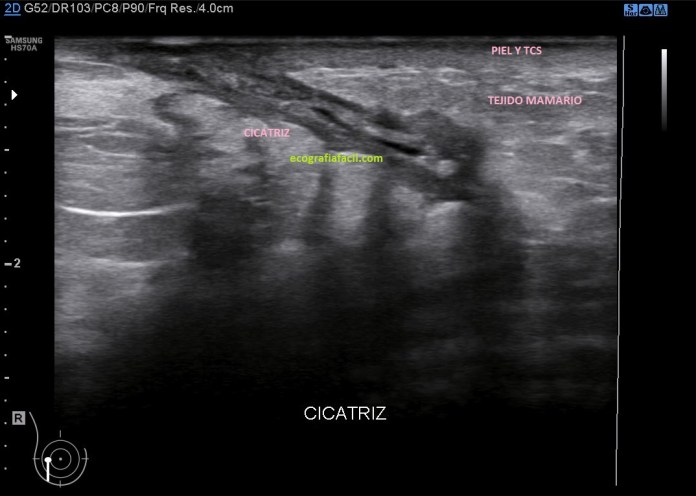

En la primera revisión tras cirugía nos encontramos una lesión cicatricial con una moderada cantidad de líquido de aspecto hipoecogénico, es irregular, la paciente tenía molestia en la zona, pero no presentaba fiebre.

En la segunda revisión encontramos un lecho quirúrgico mucho más pequeño, con una lengüeta de líquido, en la mitad de la cicatriz interna. Lo llamativo de este caso es que el líquido no está embolsado, sino que está buscando una salida, simulando a un trayecto fistuloso y en realidad tenía un comportamiento similar porque la paciente podía autodrenarse el contenido, drenaje que en ocasiones era autónomo.

En la segunda exploración observamos que el líquido ha disminuido mucho de tamaño y que su aspecto ecográfico es anecoico. En cualquier caso existía una clara mejoría radiológica entre ambos estudios por lo que se derivó a la paciente para valorar en la consulta de unidad de mama para eventualmente iniciar tratamiento para cerrar si definitivamente ese seroma y evitar complicaciones posteriores.